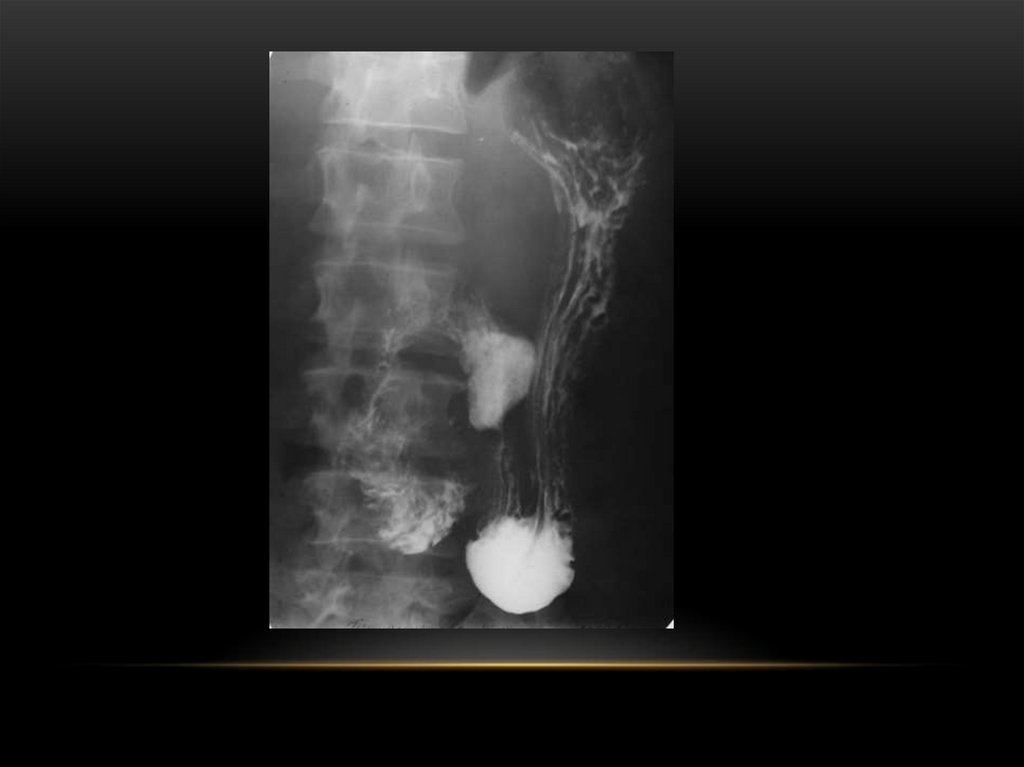

Пациент Д. 1955 г.р.

Заключение:

Экзофитный Cr нижней

трети грудного отдела

пищевода.